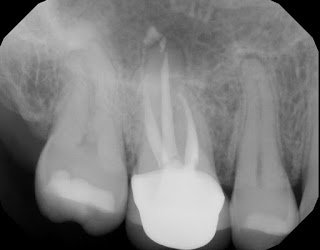

5 year recall of the tooth finds it fully functional and asymptomatic. Note the fine margins of the crown which play a key role in the success of this treatment. Some patients will elect to retain a natural tooth with a crack, understanding the guarded long term prognosis, rather than extract and replace it immediately.